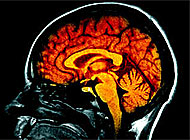

The brain, a 1.5 kilogramme mass of interwoven nerve cells, determines who we are by governing our emotions, intelligence, creativity and actions. It is more complex and versatile than any computer, and scientists are still trying to unravel its mysteries.

The brain holds the answers to many of today’s least understood disorders, including stroke, Alzheimer’s Disease, Parkinson’s Disease, depression, stress, eating disorders, schizophrenia and autism.